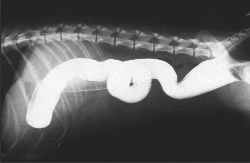

医药级硫酸钡

医药级 硫酸钡